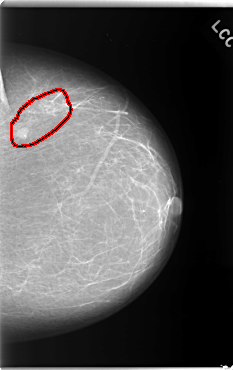

C_0132_1.LEFT_CC

FILE: C_0132_1.LEFT_CC.OVERLAY

TOTAL_ABNORMALITIES 1

ABNORMALITY 1

LESION_TYPE CALCIFICATION TYPE PLEOMORPHIC DISTRIBUTION CLUSTERED

LESION_TYPE MASS SHAPE OVAL MARGINS CIRCUMSCRIBED

ASSESSMENT 4

SUBTLETY 5

PATHOLOGY MALIGNANT

TOTAL_OUTLINES 1

BOUNDARY